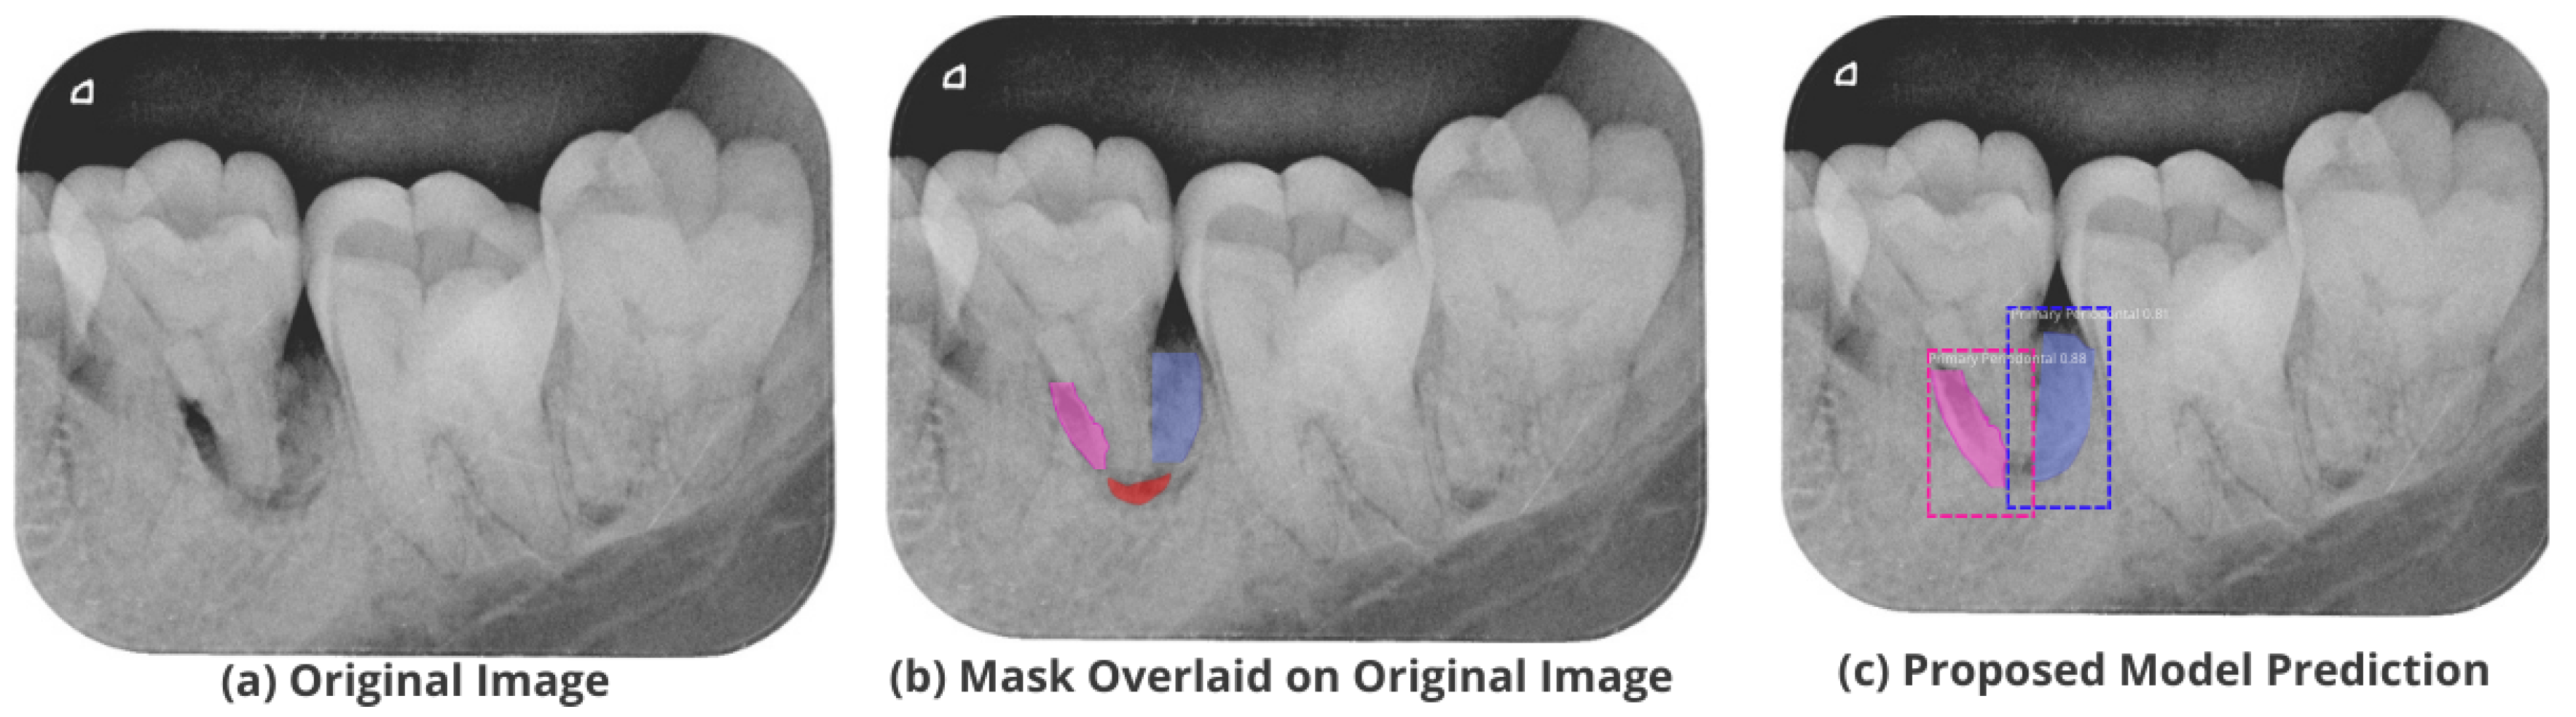

3.5. Comparison with Test Images

The proposed model accurately predicts and localizes the lesions as depicted in Figure 10, Figure 11, Figure 12, Figure 13 and Figure 14. The results indicate that the model makes predictions similar to that of the annotated masks using the periapical radiographic images. Additionally, the proposed model was evaluated based on performance indicators like precision, recall, F1 score, and accuracy for each classified periodontal lesion. The obtained results indicate that the proposed backbone network provides good performance for disease classification. All the test images for the proposed study show a 95% confidence level indicating that the database annotations are in the right direction.

Figure 12.

Test performance for the localization of a ’Primary Perio and Secondary Endo’ lesion.

Figure 13.

Test performance for the localization of a ’Primary Periodontal’ lesion.